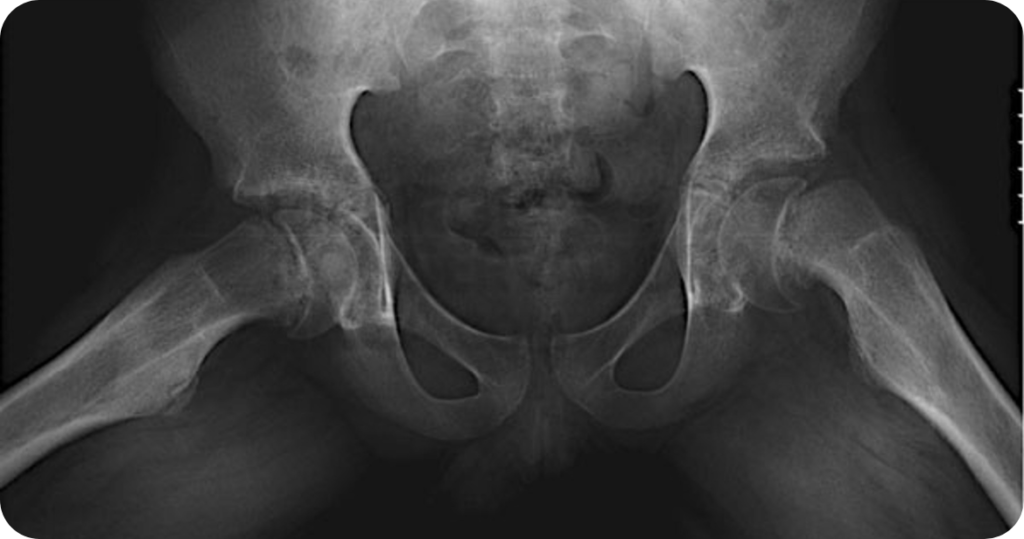

O diagnóstico é confirmado por exames de imagem, principalmente o raio-X do quadril. Em situações específicas, podem ser usados exames complementares, como tomografia ou ressonância magnética.